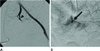

Fig. 3

A 47-year-old man who had pelvic bone fracture due to crushing injury.

A. Selective left internal iliac arteriogram shows abrupt obstruction of anterior division (arrowhead). It suggests transection of the artery. However, we ignored the finding at that time.

B. Delayed angiographic image of the same artery shows stasis (arrow) of contrast media. It reveals traumatic arterial injury.